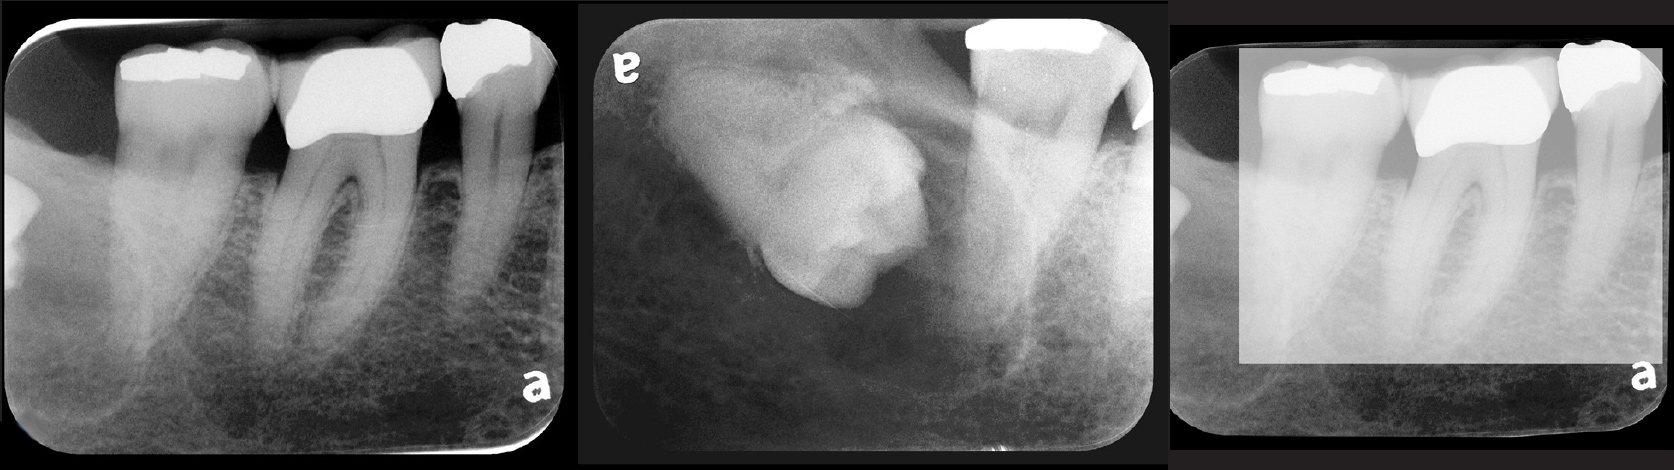

Fig 2. Left: PSP vertical PA radiograph of

maxillary bicuspid area demonstrating full root structure, several millimeters of bony anatomy beyond apices and maxillary sinus. Tooth No. 4 may be

traumatized as periodontal ligament is widened. Right: PSP horizontal PA radiograph of maxillary bicuspid area. Tooth No. 12 shows widened apical

periodontal ligament presumably caused by deep restorative filling. Some loss of supporting bone is evident interproximally, especially pronounced

between tooth Nos. 14 and 15.

Figure 2

Fig 3. Two PSP PA radiographs of mandibular teeth showing: left, the initial view

of molar area and suspected pathology surrounding impacted tooth No. 32; center,

subsequently exposed PA radiograph, placed more distally, demonstrates extent

of large cyst as well as entire tooth and root No. 32. Proper alert as to presence

of suspected cyst and appropriate referral for 3D CBCT study and surgical

enucleation was given to the patient. Right: Same radiograph as on the left, but

with lighter superimposed outline of the area that would be visible using an HW

sensor rather than a PSP sensor. The small area of pathology is likely obscured

because it is visually overlaid by the root of tooth No. 31. Neglect of this significant

pathology may have resulted.

Figure 3